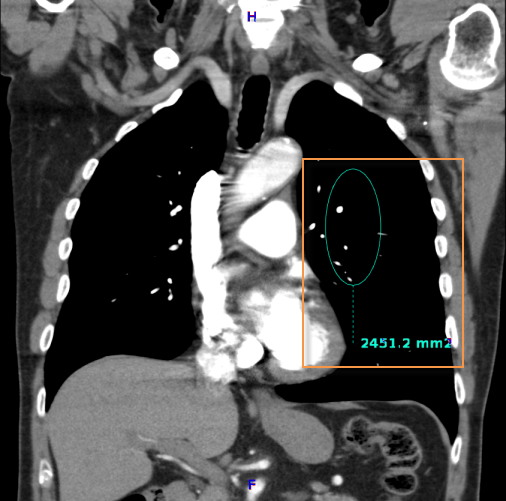

A vizsgált terület (ROI) mérésének menete:

Válassza a vizsgált terület (ROI) ![]() ikont

ikont

Kattintson a vizsgált területre

Húzza az egeret a terület meghatározásához

Engedje el az egérgombot

A középső fogóponttal  mozgathatja az ROI-t a képen, a többivel pedig nyújthatja vagy keskenyítheti.

mozgathatja az ROI-t a képen, a többivel pedig nyújthatja vagy keskenyítheti.